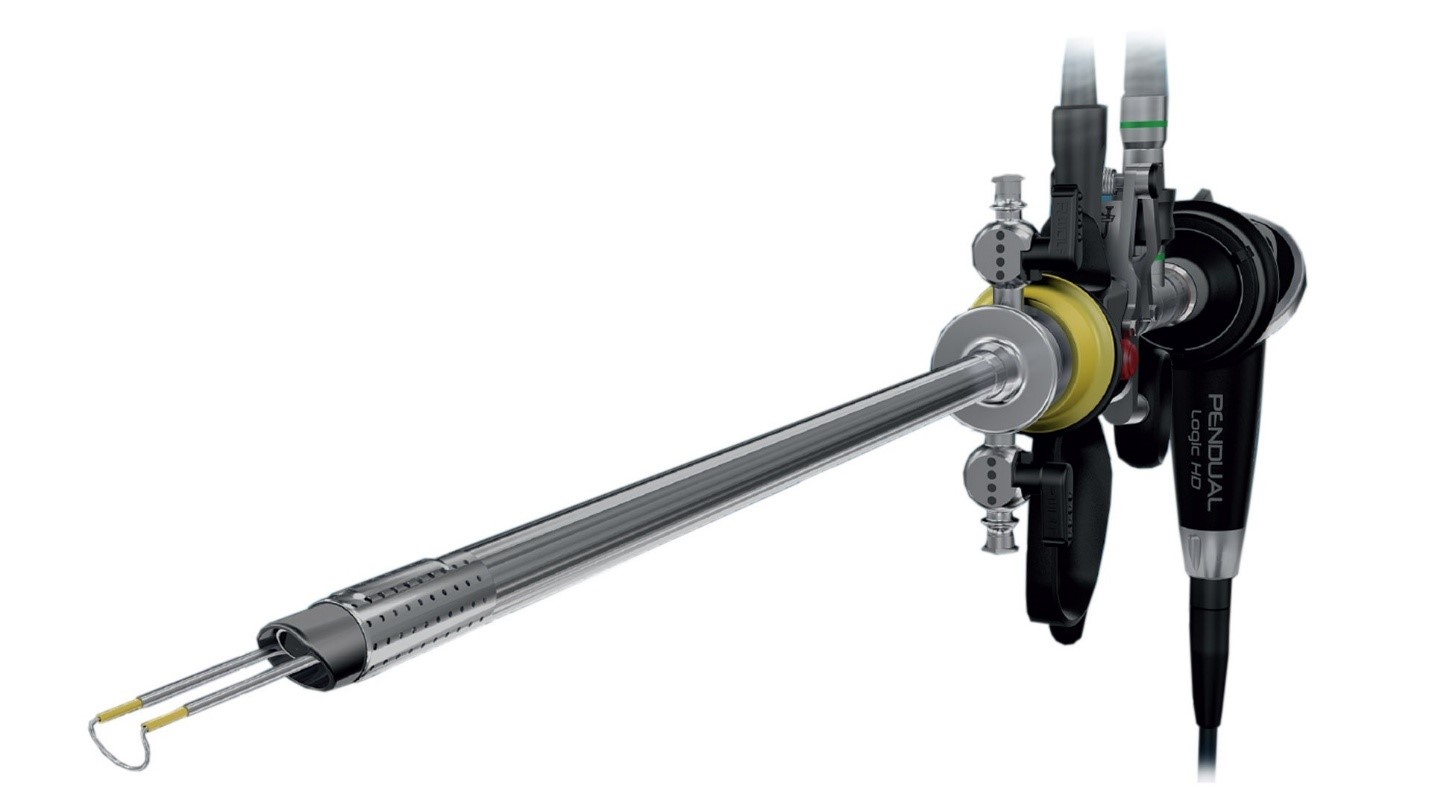

Операция ТУР выполняется резектоскопом, это трубка диаметром от 7,3 мм до 9 мм и длиной 30 см, которая вводится в мочеиспускательный канал. Внутри трубки находятся два подвижных изолированных электрода, к концам которых прикреплена проволока из материала с высоким удельным сопротивлением в виде петли диаметром обычно около 4 мм:

Через трубку резектоскопа подается ирригационная жидкость (физраствор) для охлаждения и очистки рабочей области от крови и срезанной ткани. Срезанные кусочки ткани под действием струи ирригационной жидкости выносятся в мочевой пузырь, где накапливаются до окончания операции. Удаляются они из мочевого пузыря через резектоскоп или отсасываются с помощью шприца Тьефеля. Крупные фрагменты удаляются с помощью специального захвата.

На конце резектоскопа установлена видеокамера и осветительный прибор, что позволяет отображать весь процесс на экране большого монитора.

В резектоскоп можно вставлять различные рабочие инструменты и петли различной формы и размера. Для среза ткани петля разогревается переменным током величиной 0,3...1,5 А и частотой 300-500 кГц. Это позволяет избежать стимуляции током мышц или нервов. Петля разогревается до красного или белого свечения в режиме резания при напряжении 100-300 В и до 200-400 В в режиме коагуляции (остановки кровотечения путем запаивания сосудов). Напряжение и ток подаются в форме импульсов с регулируемой скважностью. Регулировка параметров может выполняться оперативно в процессе операции.